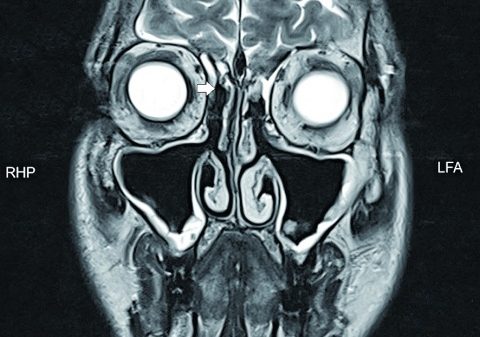

Die chirurgische Behandlung infektiöser Erkrankungen am Thorax ist elementarer Bestandteil sowohl der Thorax- als auch der Herzchirurgie. In diesem Beitrag werden das Pleuraempyem, die deszendierende Mediastinitis und die Sternumosteomyelitis nach herz-/thoraxchirurgischen Eingriffen exemplarisch dargestellt.

Wichtig für den Erfolg der Behandlung bei allen septischen Krankheitsbildern am Thorax sind rechtzeitiges Erkennen und zügige Therapieeinleitung. Die Grundprinzipien entsprechen denen anderer Infektionen in der Chirurgie: Chirurgische Sanierung und Drainage des lokalen Entzündungsfokus sowie eine resistenzgerechte systemische Antibiotikatherapie. Die minimal-invasive Chirurgie hat dabei sowohl in der Behandlung der septischen Krankheitsbilder als auch in der Verhinderung postoperativer septischer Komplikationen ihren Stellenwert.